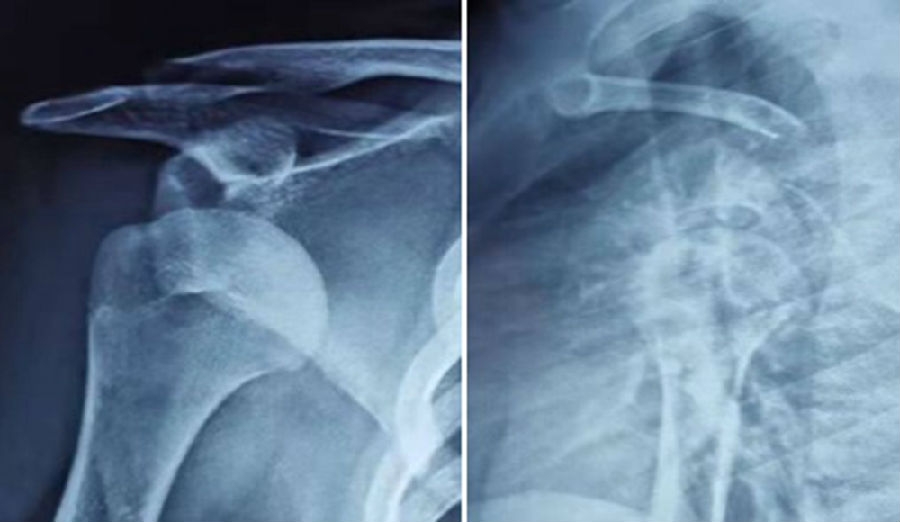

典型病例,王XX,男性,15岁。主诉右肩外伤疼痛、活动受限1月。既往半年前有肩关节脱位病史。

图37 既往肩关节脱位时,急诊所拍的X线片

图38 复位后的肩关节CT

视频6-7(拼在一个画面里,左右并排) 术前查体,ISIS评分6分

图39 此次复发脱位MR评估

图40 影像学评估

双侧CT三维扫描显示:D=34mm,d=3mm,d/D=肩胛盂骨缺损9%;GT=25.2mm,HIS=30mm。

该患者为轨迹外Hill-Sachs损伤,需要做bankart修补,同时轨迹外做remplissage手术。